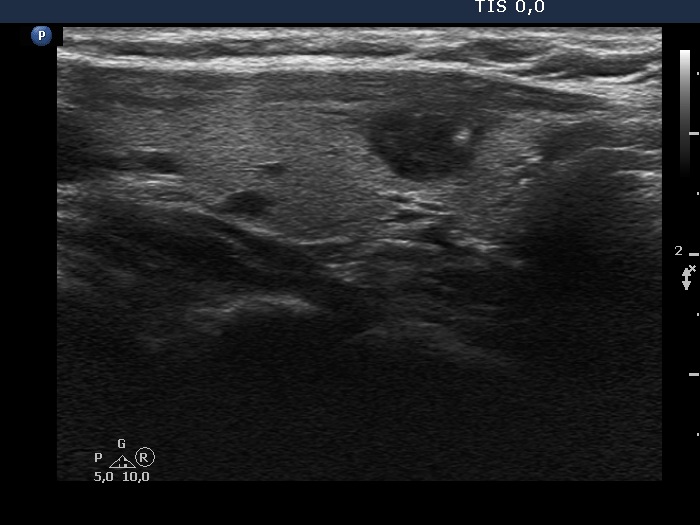

First examination (first and second rows of images)

Clinical presentation: A 39-yr old woman was referred for evaluation of a thyroid cyst which has refilled twice in the past. On the last aspiration, 2 years ago the maximal diameter of the nodule was 24 mm.

Palpation: no abnormality.

Laboratory test: 2.71 mIU/L.

Ultrasonography. The thyroid was echonormal. There was a central-type cystic nodule in the left lobe. The solid portion was echonormal-minimally hypoechoic. The lesion showed back wall cystic figures.Cytology was performed from the lesion in the left lobe and resulted in benign, cystic-colloid goiter.

Suggestion. Ultrasound in two years, in the event of complaints at once. If the cyst would recur ethanol sclerotherapy is advised.